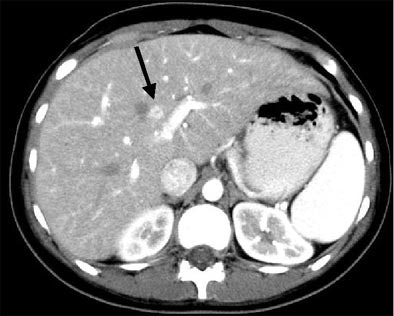

"This example of a type 4 hyperdense lesion on arterial-phase (CT) is not seen on the portal-venous phase, and the follow-up arterial-phase (scan) performed a few weeks later shows that the type 4 lesion had changed its morphology to a type 2 lesion, with a central hypodensity and peripheral hyperdense rim," he said.

| Immunocompromised patient after prolonged neutropenia with fever and candidemia. Type 4 lesion on arterial phase (above) is not seen on portal-venous phase (below). The lesion was also not visualized in arterial-phase CT performed a few weeks earlier (bottom), indicating a new lesion. |

![]() |